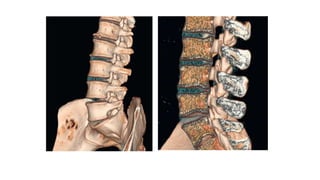

This three-dimensional reconstruction from computed tomography (CT) axial images focuses on the occipital–

cervical junction and the C1-2 (atlantoaxial) junction

The skull base has been cut away nearly completely in this

CT model, allowing the ring of C1 and its relationship to the

dens of C2 to be seen in detail.

C1 and C2 view of the normal cervical spine

This three-dimensional reconstructionfrom computed tomography (CT) axial images focuses on the occipital– cervical junction and the C1-2 (atlantoaxial) junction

The skull basehas been cut away nearly completely in this CT model, allowing the ring of C1 and its relationship to the dens of C2 to be seen in detail. C1 and C2 view of the normal cervical spine